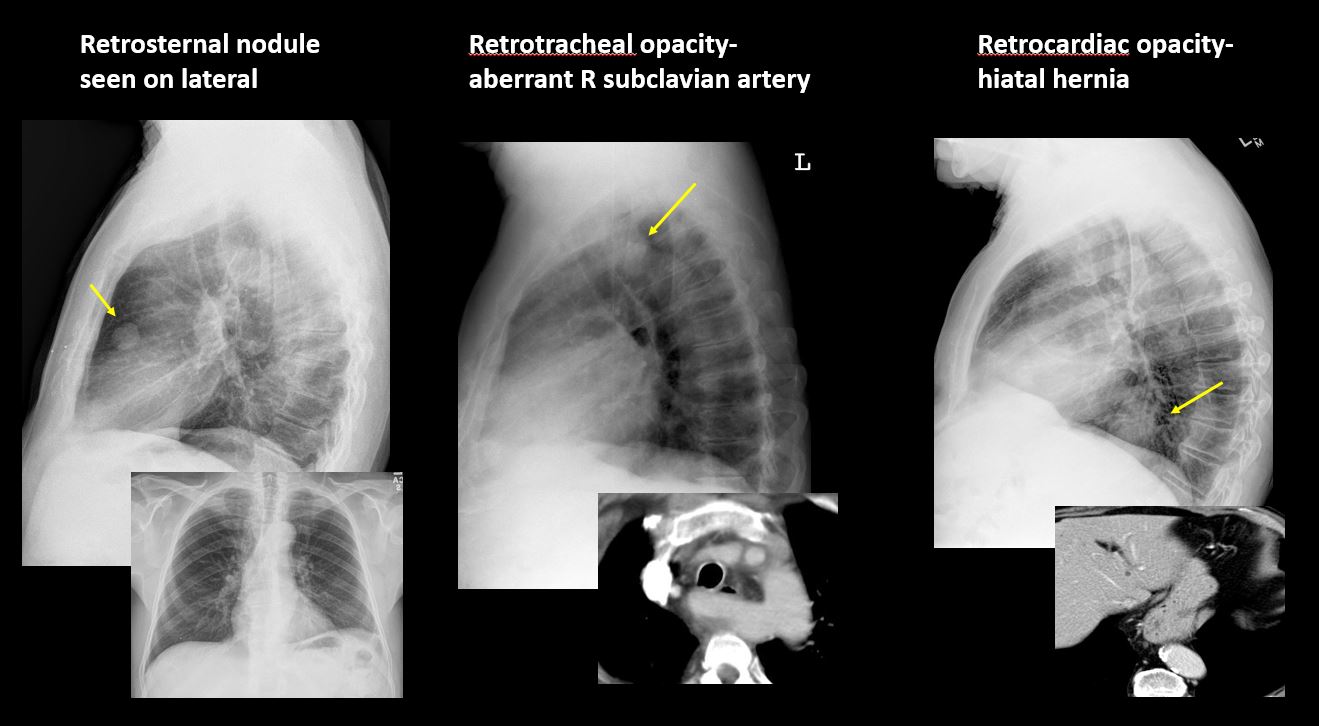

There is an abnormality in the retrosternal, retrotracheal, or retrocardiac space on the lateral view. [Yes/No]